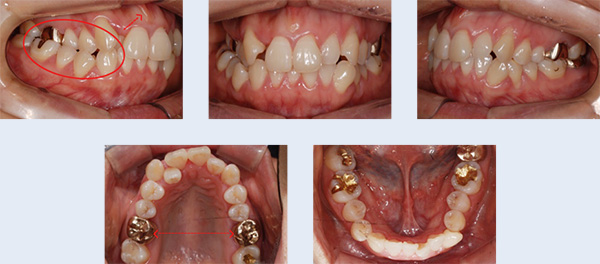

2년 전 식립한 임플란트의 보철물이 탈락된 상태로 1년간 지내오신 25세 여성입니다. 임플란트 식립을 위해 사용한 인공 뿌리를 제거하고 치아가 가지런해 지길 원하셨습니다. 자연치아로만 치료를 진행할 수 있도록 하기 위해 인공 뿌리를 제거하고, 빈 공간으로 치아를 이동시켰습니다.

① Trephine Drill과 bur를 이용하여 임플란트 fixture 제거

② 결손 부위의 치조골 내로 후방 어금니들의 뿌리가 위치되도록 이동 및 조절

임플란트 제거 후 생긴 빈 공간으로 브라켓을 부착한 사랑니를 이동시켜 추가적인 임플란트 식립이나 보철 치료 없이도 자연스러운 치열을 갖게 되었습니다.